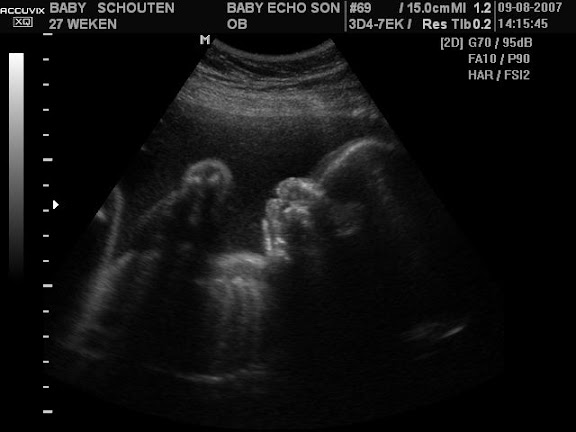

mag ik jullie voorstellen aan onze frutsel

dank je be

Popples leuk zo'n frutseltje zien!

die 3 en 4D echo's zijn gaaf ja zeker als je optijd bent dan heeft de kleine nog ruimte, en niet alle handen en voeten voor t snoetje

de echo van Popples is ook mooi duidelijk trouwens!! gaaf